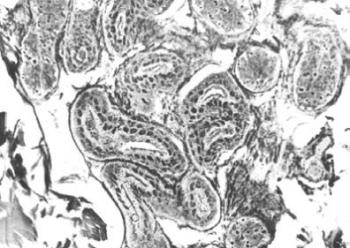

10. ábra. Verejtékmirigyek és a körülöttük lévő rácsrostozat római kori múmia fejbőréből készült metszetben. Az ezüstözéssel gyakran „előhívhatók” a más eljárásokkal fel nem tüntethető sejtmagok is. Gömöri-ezüstözés, 200× nagyítás

14. ábra. A vese glomerulusai, a kanyarulatos csatornák alapi hártyája, valamint a csatornákban lévő cilinderek jól festődnek PAS festéssel. 71 éves férfi mumifikálódott veséje, 100× nagyítás